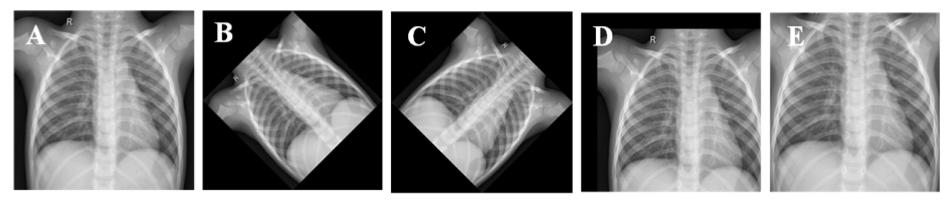

如Chowdhury等人所建议,在他们的论文中,三种增强策略(旋转、缩放和平移)可用于为COVID-19生成额外的训练图像,有助于防止“过度拟合”:https://arxiv.org/pdf/2003.13145.pdf。

原始胸部X光图像(A),逆时针旋转45度后图像(B),顺时针旋转45度后图像,水平和垂直平移20%后图像(D),放大10%后图像(E)。

使用TS/Keras图像预处理库(ImageDataGenerator),可以更改多个图像参数,例如:

trainAug = ImageDataGenerator( rotation_range=15, width_shift_range=0.2, height_shift_range=0.2, rescale=1./255, shear_range=0.2, zoom_range=0.2, horizontal_flip=True, fill_mode='nearest')

一开始,仅应用图像最大旋转15度来评估结果。